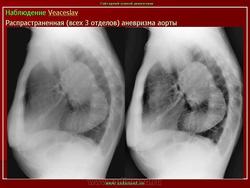

Наблюдение Tatarin